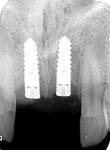

8) Kontrolní RTG snímek po operaci